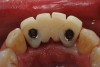

Figure 7a  Stage 1 surgery.

Figure 7a

Figure 7b  Clinical healing completed.

Figure 7b

The patient was given postoperative instructions and advised to maintain a soft diet for 6 to 8 weeks to protect the implants. The patient was followed weekly for the first 3 weeks and monthly thereafter. After 4 months of healing, the provisional restoration was removed and the soft tissues were examined. Mature, keratinized gingival tissues were present facially, lingually, and interproximally. Nonkeratinized tissue could be seen at the tissue surfaces of the ovate pontics and in the intrasulcular regions of the implant abutment units. No clinical probing depths beyond 1 mm were found adjacent to the abutments. The healed tissue represented an acceptable clinical result especially in light of the gap that had been present at the time of implant placement (Figure 7A and Figure 7B). Final impressions were made, and the permanent ceramo-metal screw-retained prosthesis was placed within 8 weeks (Figure 8).